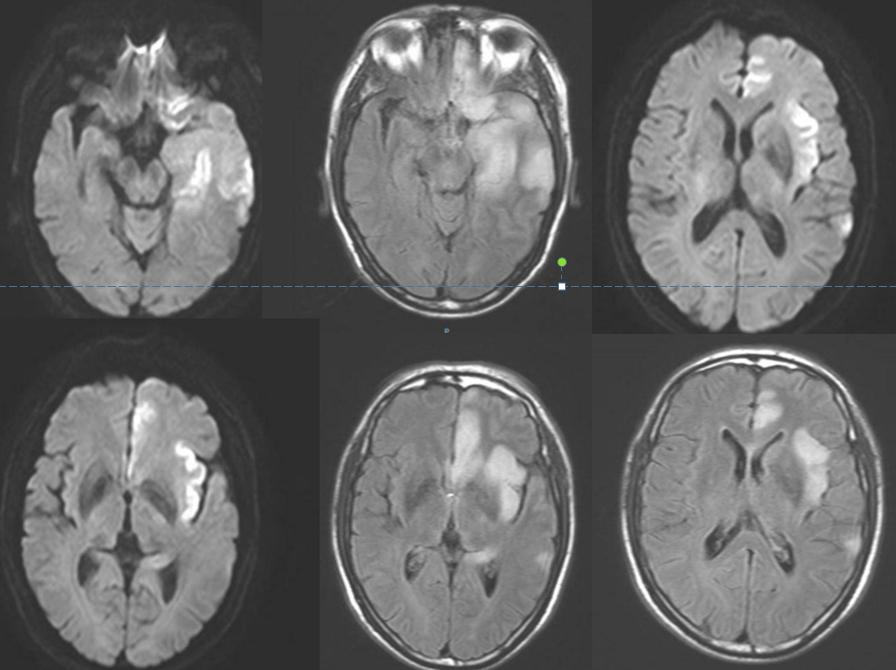

男性59岁,主因头痛发热9天,认知下降5天入院。查体:神志清,反应迟钝,记忆力下降,定向力和计算力检查不合作,肌力和肌张力基本正常。

答案:单纯疱疹病毒性脑炎。复查后如下:

单纯疱疹病毒性脑炎(HSE)是由单纯疱疹病毒(herpessimplexvirus,HSV)感染引起的一种急性CNS感染性疾病,又称为急性坏死性脑炎。HSV有两种血清型,即HSV-1和HSV-2。在人类大约90%HSE由HSV-1引起。仅10%由HSV-2所致,且HSV-2所引起的HSE主要发生在新生儿,是新生儿通过产道时被HSV-2感染所致。神经节中的神经细胞是病毒潜伏的主要场所,HSV-1主要潜伏在三叉神经节,HSV-2潜伏在骶神经节。当人体受到各种非特异性刺激使机体免疫力下降,潜伏的病毒再度活化,通过嗅神经和三叉神经侵入脑组织,常选择性损害额叶基底部和颞叶,不损害豆状核。临床常见症状有:头痛、呕吐、轻微的意识和人格改变、记忆丧失、轻偏瘫、偏盲、失语、共济失调、癫痫发作、多动(震颤、舞蹈样动作、肌阵挛)、脑膜刺激征等。精神行为异常可为首发或唯一症状。单疱病毒性脑炎MR表现以双侧颞叶、额叶受累为主,脑岛及海马均受累,病变均与豆状核分界清楚,以外囊为界。